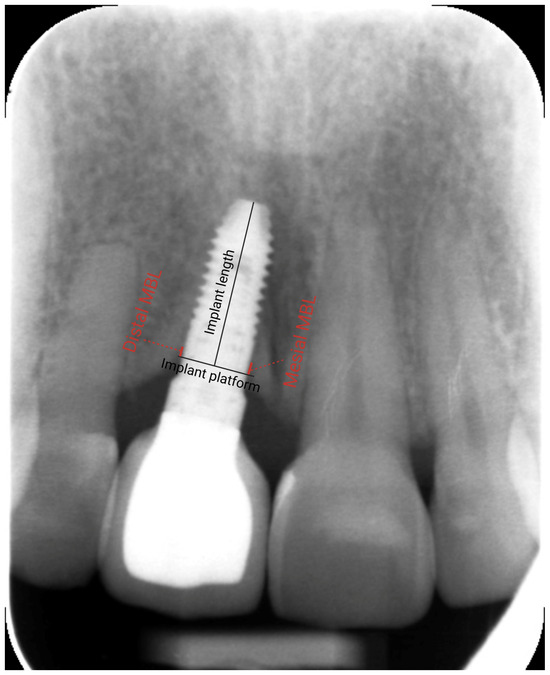

| Mesial MBL (mm) (mean ± SD) | Loading | 0.7 ± 1.0 |

| Distal MBL (mm) (mean ± SD) | 0.4 ± 0.9 | |

| Mesial MBL (mm) (mean ± SD) | Last radiograph | 0.0 ± 0.9 |

| Distal MBL (mm) (mean ± SD) | −0.1 ± 0.6 | |

| Variation in MBL–mesial (mm) (mean ± SD) | −0.7 ± 0.9 | |

| Variation in MBL–distal (mm) (mean ± SD) | −0.5 ± 0.7 | |